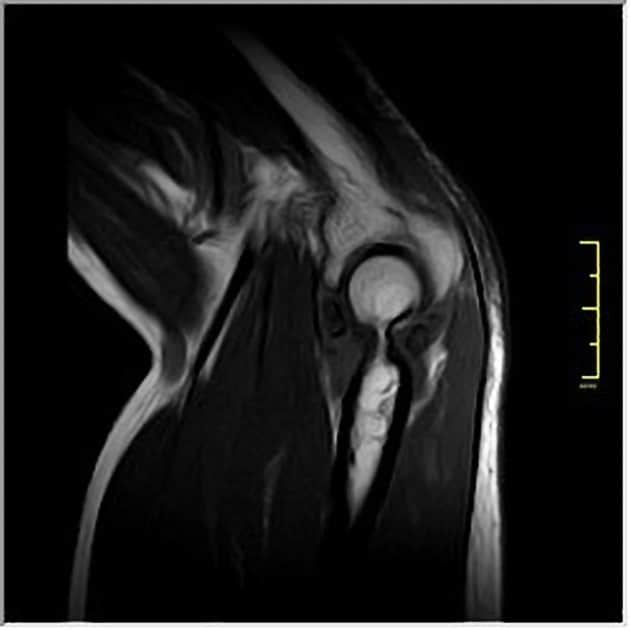

U sụn màng hoạt dịch

» Thông tin: Nữ giới – 32 tuổi.

» Lâm sàng: Đau khuỷu tay 2 năm.